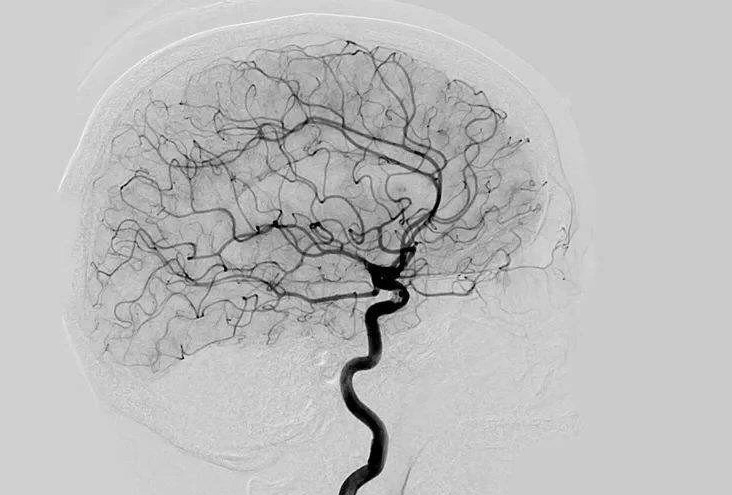

Digital Subtraction Angiography 血管造影機又稱數(shù)字減影血管造影機,是通過電子計算機進行輔助成像的血管造影方法,應(yīng)用計算機程序進行兩次成像完成的。在注人造影劑之前,第一次成像工作,圖像轉(zhuǎn)成數(shù)字信號儲存,注人造影劑后,再次成像并轉(zhuǎn)換成數(shù)字信號,兩次數(shù)字相減,消除相同的信號,得到只有造影劑的血管圖像。臨床主要應(yīng)用于冠心病、心律失常、瓣膜病和先天性心臟病的診斷和治療。